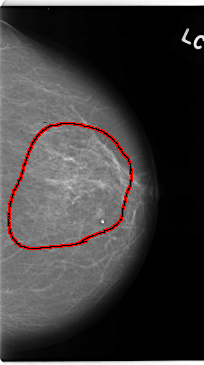

C_0138_1.LEFT_MLO

LEFT_MLO LINES 4720 PIXELS_PER_LINE 2672 BITS_PER_PIXEL 12 RESOLUTION 50 OVERLAY

FILE: C_0138_1.LEFT_MLO.OVERLAY

TOTAL_ABNORMALITIES 1

ABNORMALITY 1

LESION_TYPE CALCIFICATION TYPE AMORPHOUS DISTRIBUTION REGIONAL

ASSESSMENT 5

SUBTLETY 3

PATHOLOGY MALIGNANT

TOTAL_OUTLINES 1

BOUNDARY